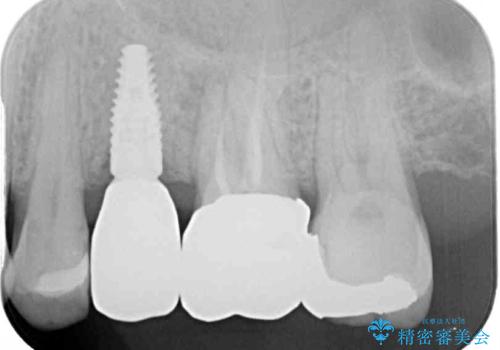

より審美的で、より機能的に優れた治療をご希望とのことであったので、ジルコニアカスタムアバットメントを用いたインプラント治療を行うこととしました。

ジルコニアカスタムアバットメントは、歯肉ラインに金属が見えにくいというだけでなく、クラウンを装着する土台の形が天然歯と近い形態となるため、清掃性が高く歯肉が腫れにくいというメリットがあります。

インプラントは、骨との生着能が比較的高いとさせるSLAタイプを使用しました。